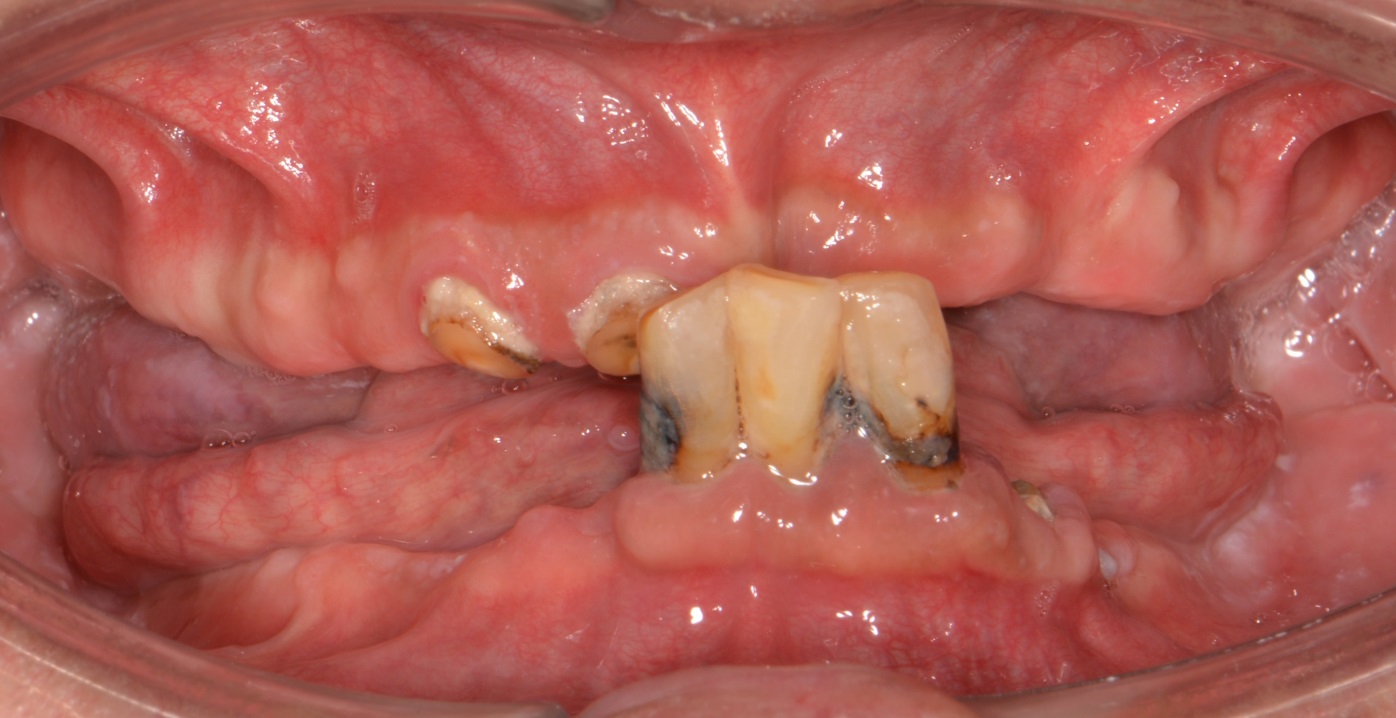

상,하악 완전틀니

Before

안 좋은 치아를 모두 발치하고,

상,하악 모두 완전 틀니로 진행하였습니다.

완전틀니는 걱정하시는 것보다 심미적이고 이쁩니다. ^^